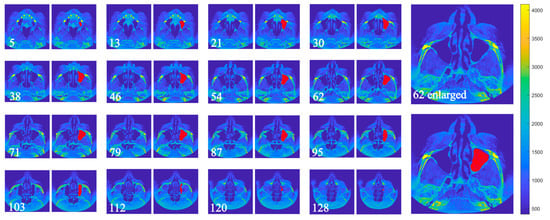

2.2. Algorithm for Detection of the Maxillary Sinus

- Maxillary sinus identification in each image: For a given image, surfaces associated with the sinus volume are determined by checking whether pixels in the upper and lower planes are contiguous with pixels of equivalence classes in the current plane. Let be the set of equivalence classes in plane k; then

- Iterative volume refinement: After each iteration, newly detected pixels are checked for contact with previously undetected equivalence classes in adjacent slices. If such contact exists, the algorithm traverses the images in reverse to incorporate them. This process continues until no new pixels are added. Finally, the images are scanned in normal order to associate any remaining pixels with the sinus volume.